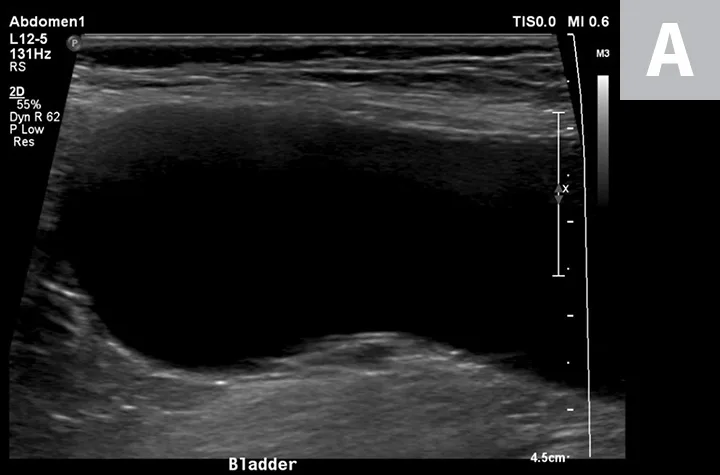

Cystocentesis is often performed with ultrasonographic guidance, although this is not required (ie, blind cystocentesis). Using ultrasonography can help direct visualization of the needle in the urinary bladder lumen, avoiding iatrogenic damage of surrounding structures (Figure 1). The relative size of the bladder, echogenicity of its contents, and any obvious structural abnormalities can also be observed. A primary advantage of blind cystocentesis is that it does not require special equipment. Cystocentesis can be challenging to perform in patients that have abdominal effusion and should be performed with ultrasonographic guidance in such cases.

Ultrasonographic image showing the cranial aspect of the urinary bladder (A), identified just before ultrasound-guided cystocentesis. It is important to adjust the depth of the image so that the urinary bladder is focused and to consider the depth of the urinary bladder using a machine scale that should be present on the ultrasound screen; in smaller patients the needle may only be partially inserted and not reach the hub (B; arrow).